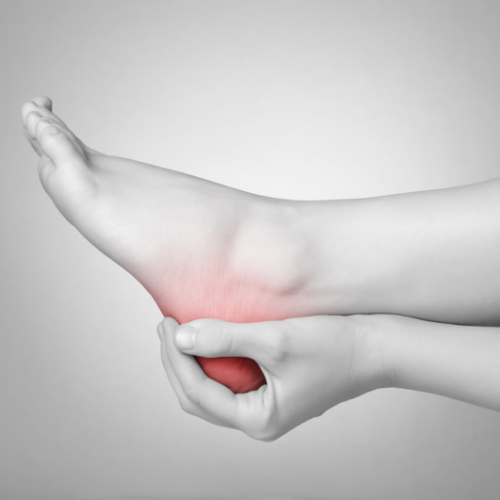

Πελματιαία απονευρωσίτιδα-άκανθα πτέρνας

Η πελματιαία απονευρωσίτιδα είναι η πιο συχνή αιτία πόνου του πέλματος. Ευθύνεται για το 80% των περιπτώσεων πόνου στην περιοχή της πτέρνας του και παρατηρείται πιο συχνά…